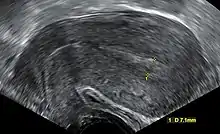

An ultrasound showing a gestational sac containing a yolk sac but no embryo

An anembryonic pregnancy (also called an "empty sac" or "blighted ovum") is a condition where the gestational sac develops normally, while the embryonic part of the pregnancy is either absent or stops growing very early. This accounts for approximately half of miscarriages. All other miscarriages are classified as embryonic miscarriages, meaning that there is an embryo present in the gestational sac. Half of embryonic miscarriages have aneuploidy (an abnormal number of chromosomes).[50]